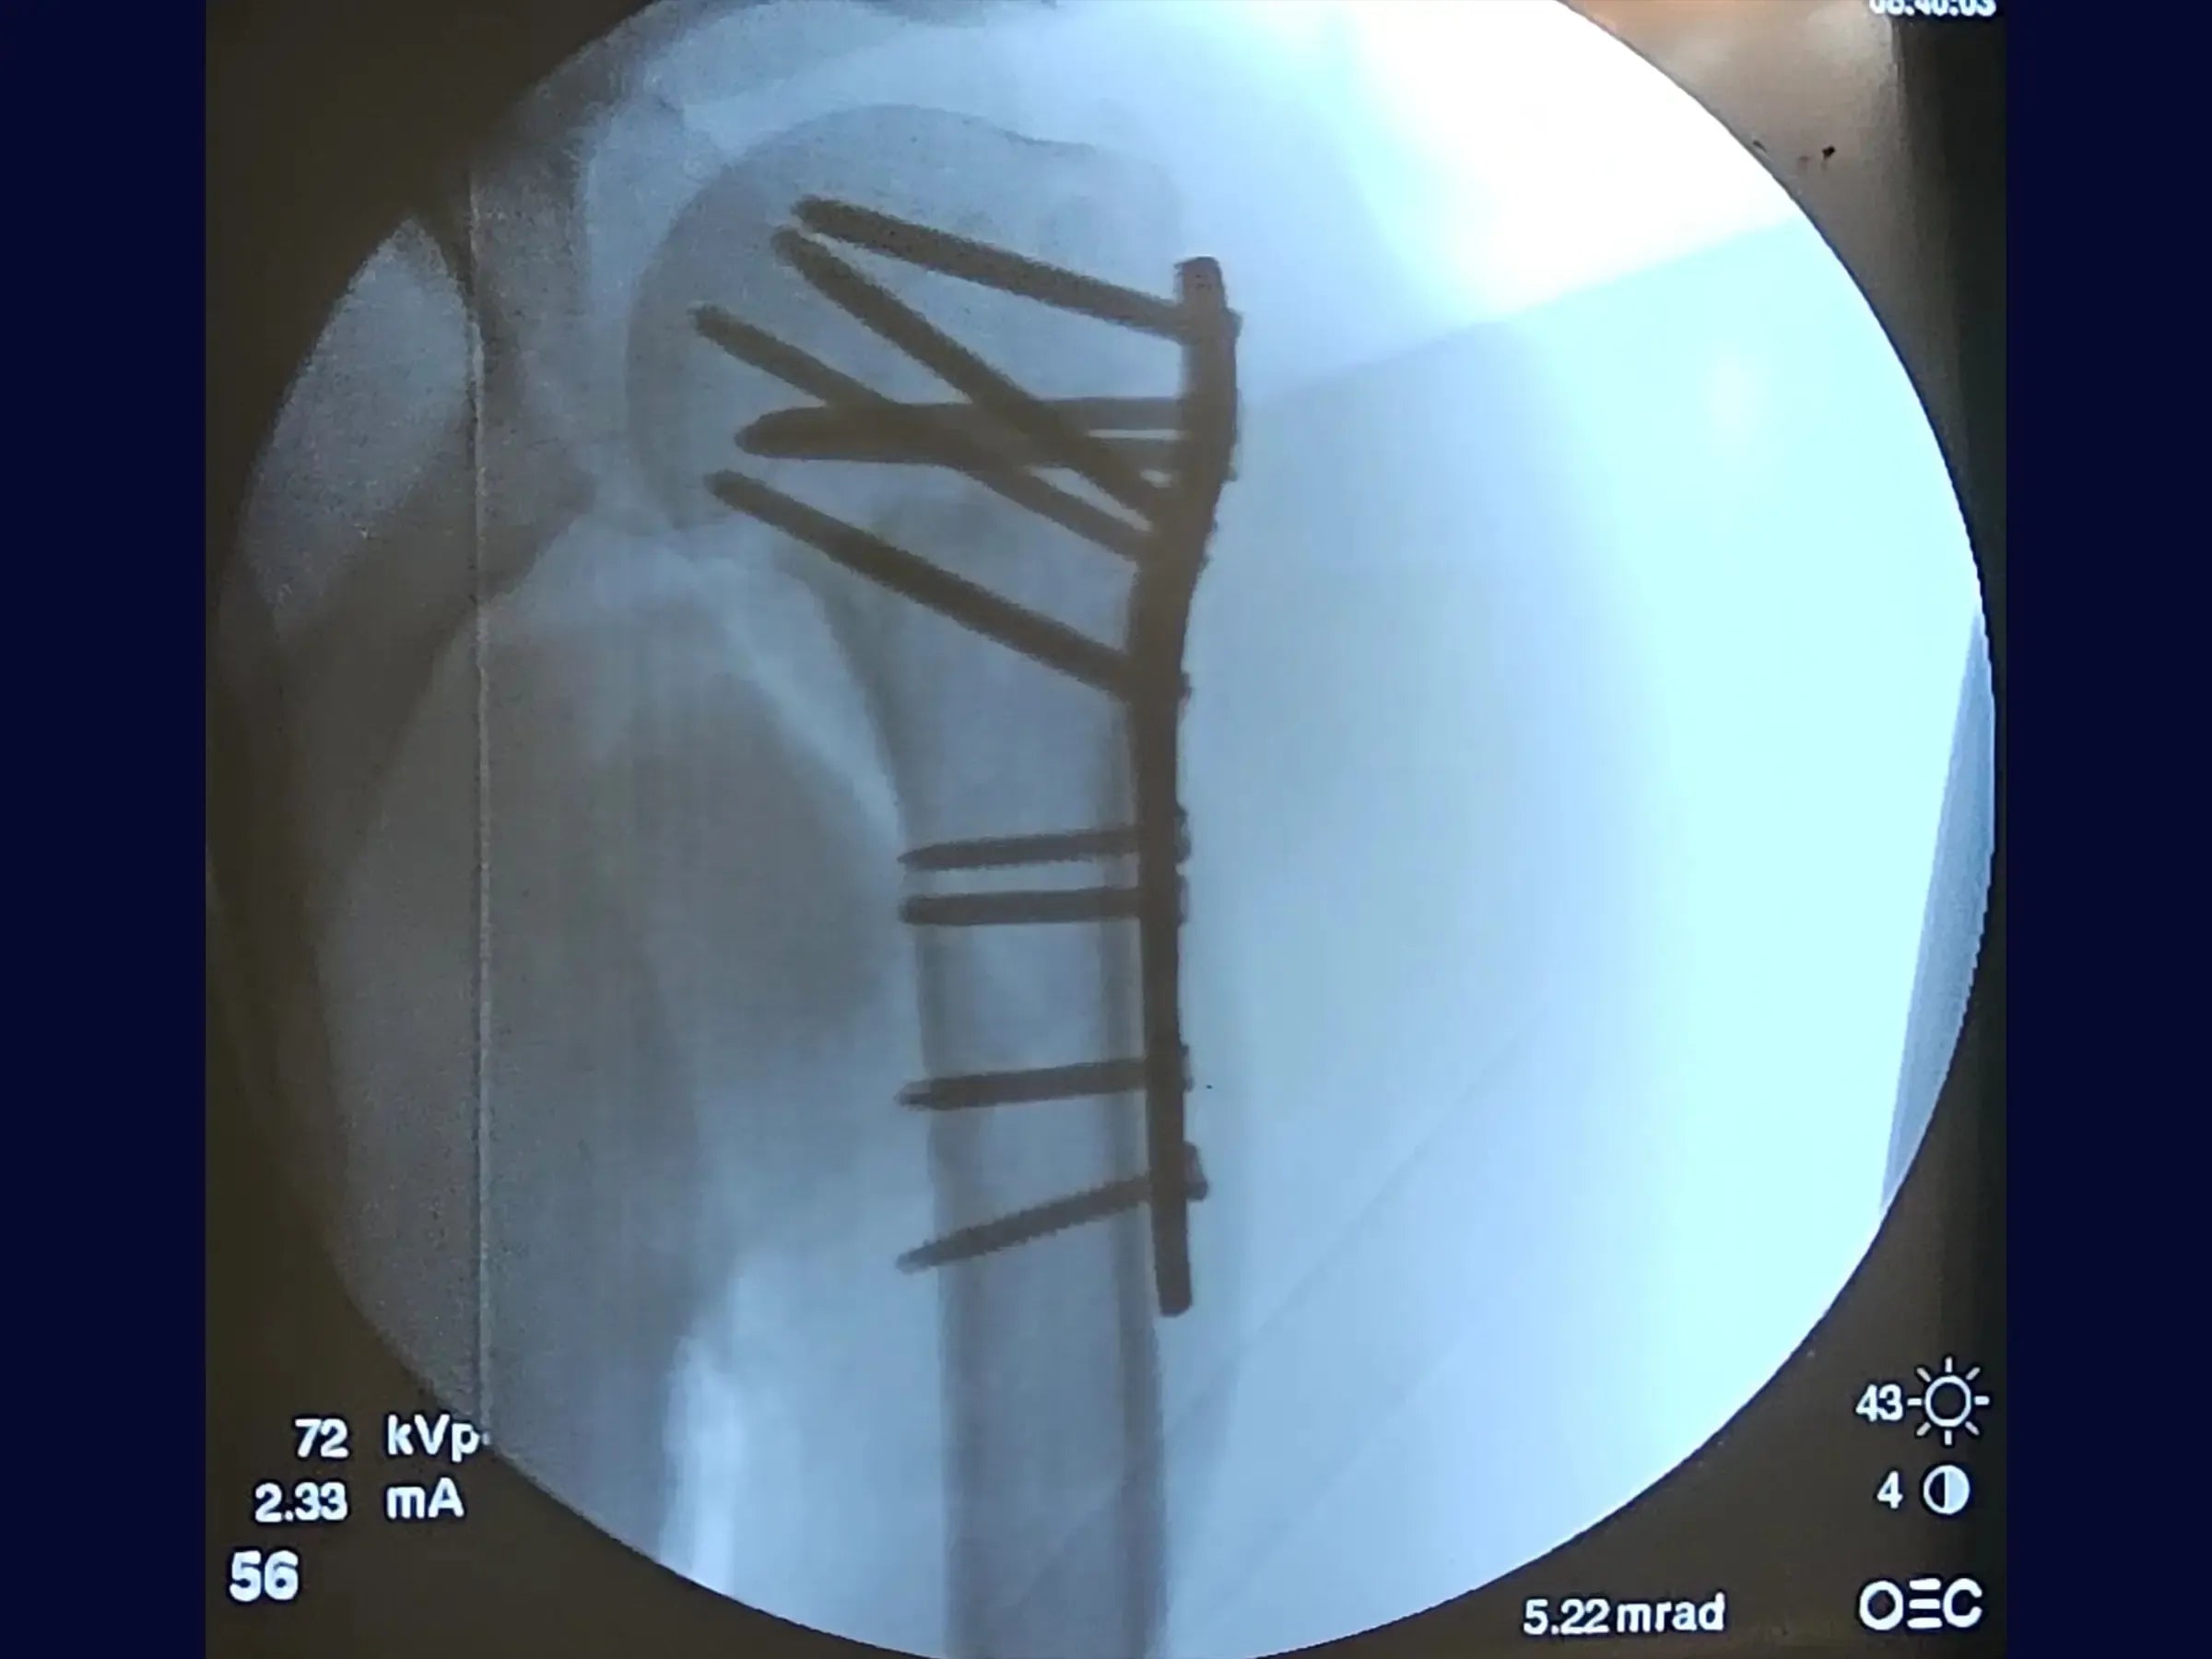

- Controle Radiográfico Intraoperatório: Análise crítica de radiografias para verificar a altura da placa, redução da fratura, e disposição dos parafusos em diferentes incidências.

- Fixação Estável com Placa: Protocolos para posicionamento da placa lateral ao sulco do bíceps e sequência de inserção de parafusos (oval, calcar, superior), garantindo estabilidade primária e secundária.